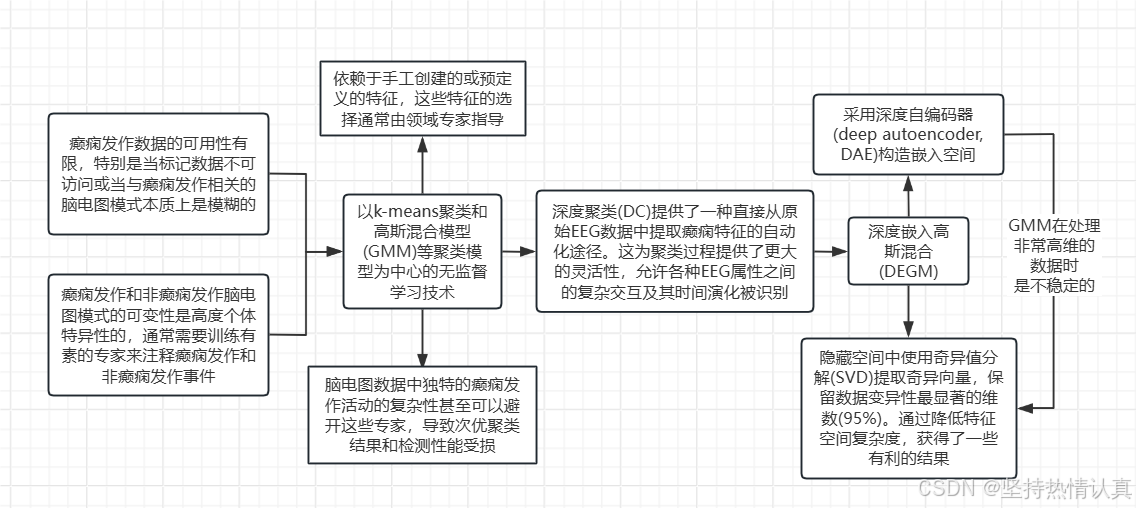

Deep Clustering for Epileptic Seizure Detection

。值得注意的是,本研究使用了一种不直接涉及标签的学习过程,与无监督方面保持一致。然而,识别无癫痫数据本质上依赖于专家标记,引入了一定程度的“部分监督”。他们取得了可以接受的结果。

Multiview Deep Subspace Clustering Networks:多视图深度子空间聚类网络

自动编码器通过将数据映射到低维空间来提取数据的特征。随着深度学习的快速发展,深度(或堆叠)自编码器在无监督学习中越来越受欢迎。深度自编码器已广泛应用于降维[36]和图像去噪[37]。

与浅层模型提取深层特征然后进行子空间聚类不同,MvDSCN将特征学习和子空间聚类结合起来,使得多视图关系影响两个部分。